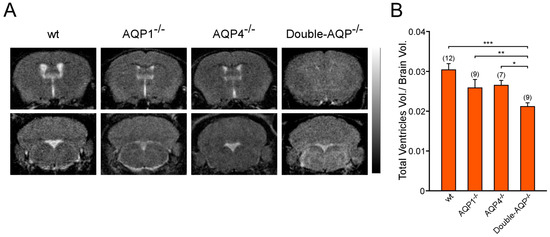

3.2. Study of the Volume and Intraventricular Pressure in the Cerebral Ventricular System